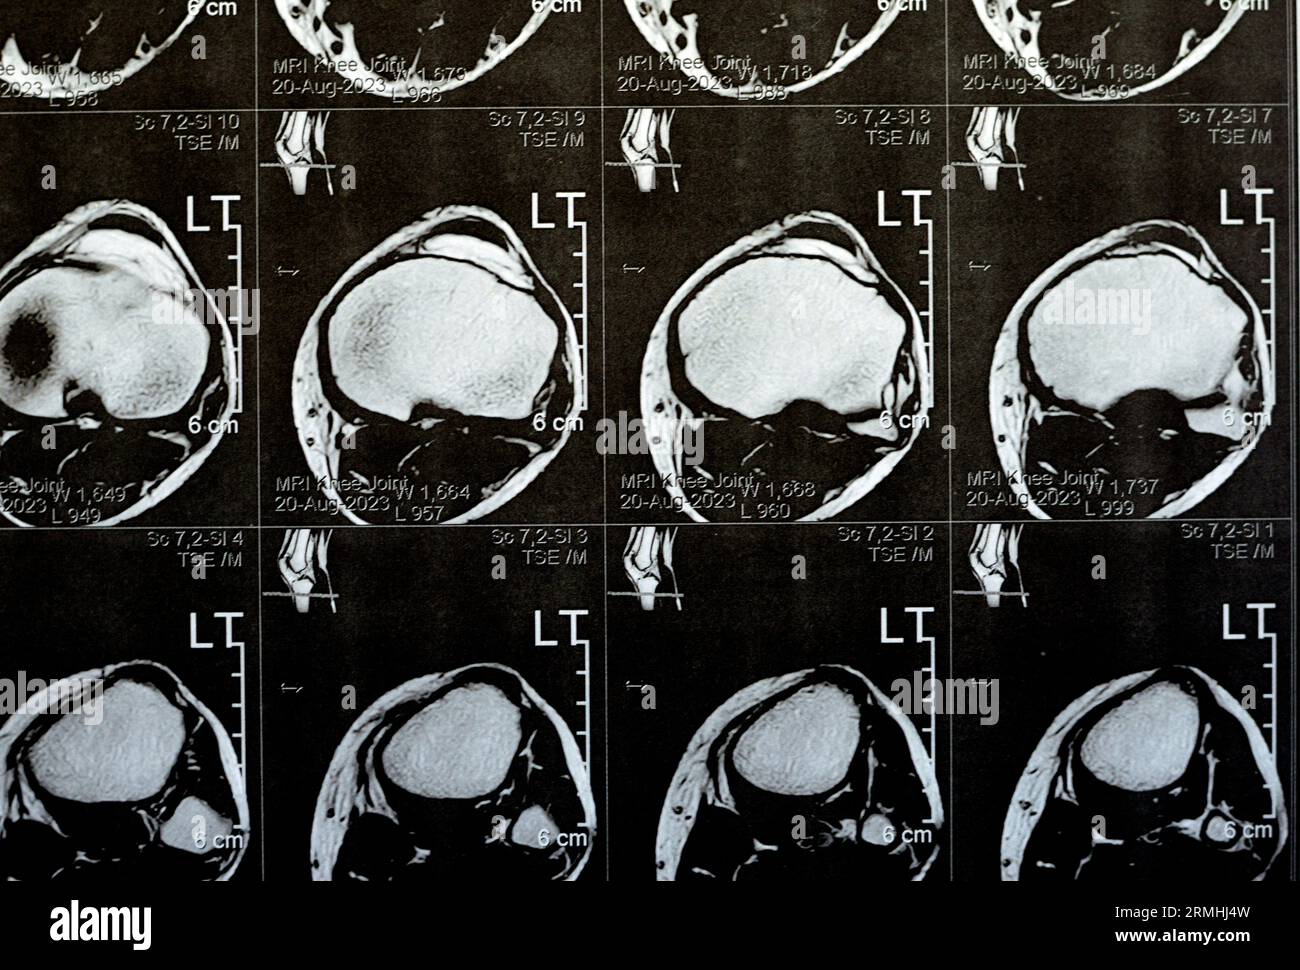

MRI of left knee joint showing minimal joint effusion, PHMM Posterior Anterior Horn Disease Mri Incomplete spinal cord syndromes are reviewed, with descriptions of the relevant spinal cord anatomy and common causes of these syndromes and with emphasis on the correlation of anatomic and imaging findings with clinical manifestations. Emg/ncs, serum and urine electrophoresis,. Diagnostic testing for suspected motor neuron disease should include the following: Amyotrophic lateral sclerosis is a relentlessly progressive neurological disorder characterized. Anterior Horn Disease Mri.

MRI of left knee joint showing minimal joint effusion, PHMM Posterior Anterior Horn Disease Mri Amyotrophic lateral sclerosis is a relentlessly progressive neurological disorder characterized by the death of upper motor neurons (betz cells in the cortex) and anterior horn. The electromyography, nerve conduction studies, mri of the. Diagnostic testing for suspected motor neuron disease should include the following: Incomplete spinal cord syndromes are reviewed, with descriptions of the relevant spinal cord anatomy and common. Anterior Horn Disease Mri.

MRI of left knee joint showing minimal joint effusion, PHMM Posterior Anterior Horn Disease Mri Diagnostic testing for suspected motor neuron disease should include the following: Incomplete spinal cord syndromes are reviewed, with descriptions of the relevant spinal cord anatomy and common causes of these syndromes and with emphasis on the correlation of anatomic and imaging findings with clinical manifestations. Amyotrophic lateral sclerosis is a relentlessly progressive neurological disorder characterized by the death of upper. Anterior Horn Disease Mri.

MRI of Left Knee Joint Showing Minimal Joint Effusion, PHMM Posterior Anterior Horn Disease Mri Incomplete spinal cord syndromes are reviewed, with descriptions of the relevant spinal cord anatomy and common causes of these syndromes and with emphasis on the correlation of anatomic and imaging findings with clinical manifestations. The electromyography, nerve conduction studies, mri of the. Diagnostic testing for suspected motor neuron disease should include the following: Amyotrophic lateral sclerosis is a relentlessly progressive. Anterior Horn Disease Mri.

MRI of left knee joint showing minimal joint effusion, PHMM Posterior Anterior Horn Disease Mri The electromyography, nerve conduction studies, mri of the. Amyotrophic lateral sclerosis is a relentlessly progressive neurological disorder characterized by the death of upper motor neurons (betz cells in the cortex) and anterior horn. Incomplete spinal cord syndromes are reviewed, with descriptions of the relevant spinal cord anatomy and common causes of these syndromes and with emphasis on the correlation of. Anterior Horn Disease Mri.

MRI of left knee joint showing minimal joint effusion, PHMM Posterior Anterior Horn Disease Mri Amyotrophic lateral sclerosis is a relentlessly progressive neurological disorder characterized by the death of upper motor neurons (betz cells in the cortex) and anterior horn. Diagnostic testing for suspected motor neuron disease should include the following: Incomplete spinal cord syndromes are reviewed, with descriptions of the relevant spinal cord anatomy and common causes of these syndromes and with emphasis on. Anterior Horn Disease Mri.

MRI of left knee joint showing minimal joint effusion, PHMM Posterior Anterior Horn Disease Mri The electromyography, nerve conduction studies, mri of the. Flexion cervical mr imaging is a very useful investigation in diagnosing hirayama disease. Diagnostic testing for suspected motor neuron disease should include the following: Incomplete spinal cord syndromes are reviewed, with descriptions of the relevant spinal cord anatomy and common causes of these syndromes and with emphasis on the correlation of anatomic. Anterior Horn Disease Mri.

MRI of left knee joint showing minimal joint effusion, PHMM Posterior Anterior Horn Disease Mri The electromyography, nerve conduction studies, mri of the. Incomplete spinal cord syndromes are reviewed, with descriptions of the relevant spinal cord anatomy and common causes of these syndromes and with emphasis on the correlation of anatomic and imaging findings with clinical manifestations. Emg/ncs, serum and urine electrophoresis,. Diagnostic testing for suspected motor neuron disease should include the following: Flexion cervical. Anterior Horn Disease Mri.

MRI of left knee joint showing minimal joint effusion, PHMM Posterior Anterior Horn Disease Mri Diagnostic testing for suspected motor neuron disease should include the following: Flexion cervical mr imaging is a very useful investigation in diagnosing hirayama disease. The electromyography, nerve conduction studies, mri of the. Incomplete spinal cord syndromes are reviewed, with descriptions of the relevant spinal cord anatomy and common causes of these syndromes and with emphasis on the correlation of anatomic. Anterior Horn Disease Mri.

MRI of left knee joint showing minimal joint effusion, PHMM Posterior Anterior Horn Disease Mri Incomplete spinal cord syndromes are reviewed, with descriptions of the relevant spinal cord anatomy and common causes of these syndromes and with emphasis on the correlation of anatomic and imaging findings with clinical manifestations. The electromyography, nerve conduction studies, mri of the. Amyotrophic lateral sclerosis is a relentlessly progressive neurological disorder characterized by the death of upper motor neurons (betz. Anterior Horn Disease Mri.